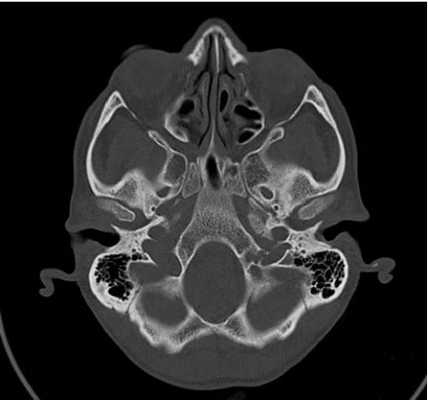

Снимок КТ основания черепа

Противопоказания для КТ основания черепа с контрастом